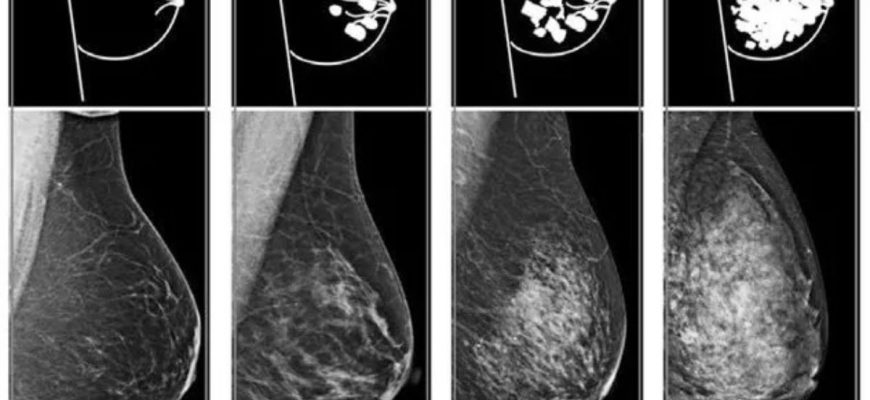

Как правильно провести анализ плотности груди: наш личный опыт и советы экспертов Когда речь заходит о здоровье женщины, одним из важных аспектов является

Как правильно провести анализ плотности груди: мой опыт и советы Когда речь заходит о здоровье женщин, особенно о профилактике и ранней диагностике заболеваний